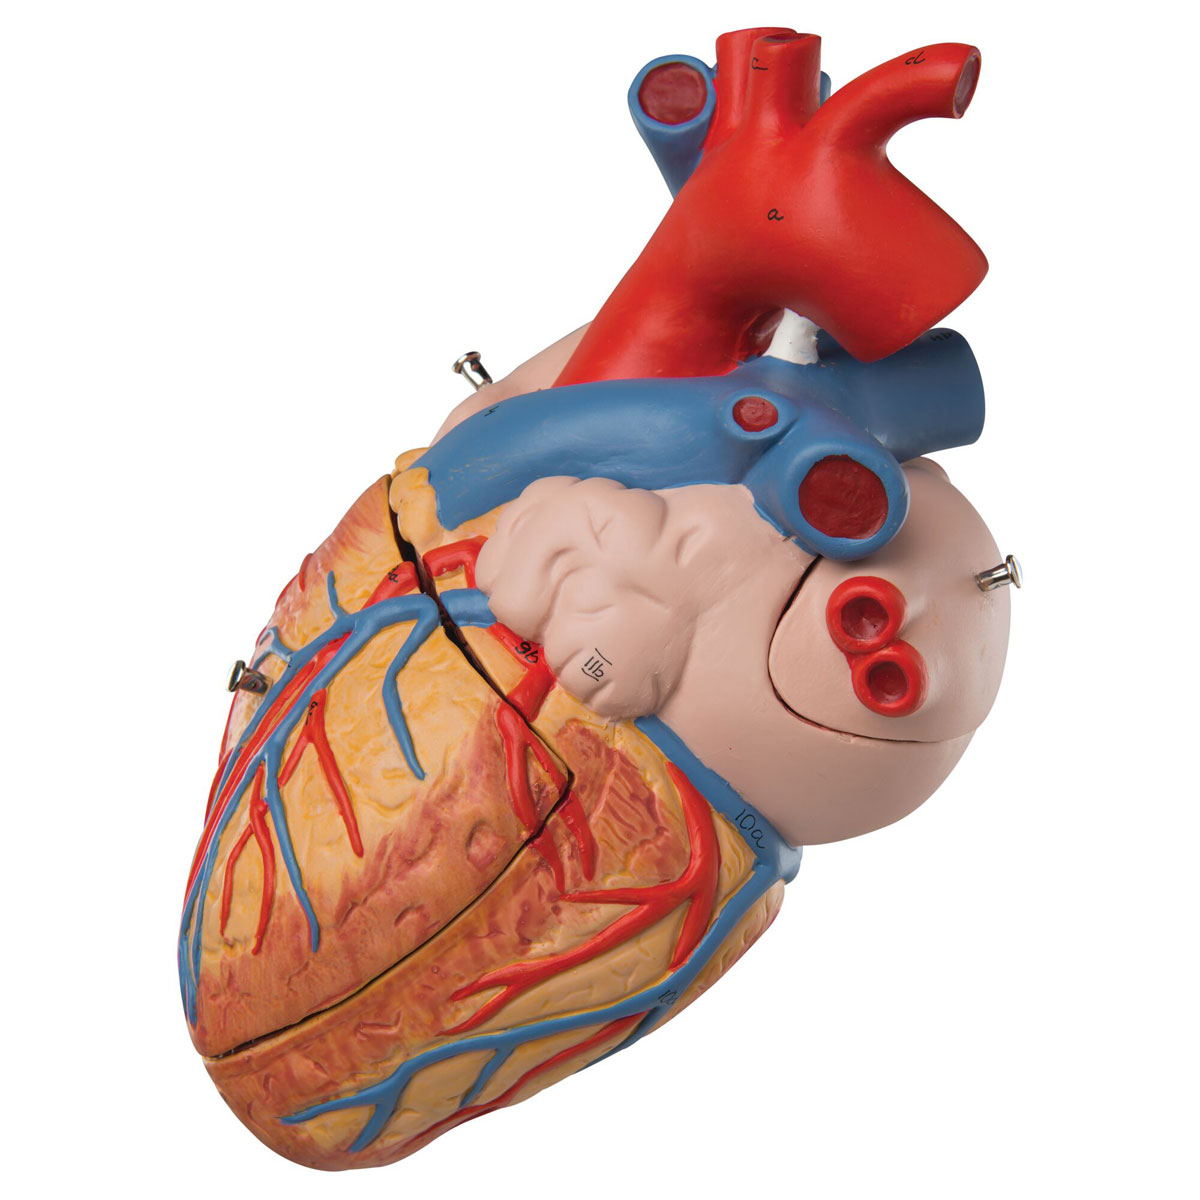

Фотографии и 3D-модели анатомии сердца человека